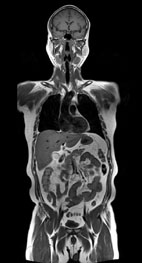

全身磁振造影從頭、軀幹到下肢清晰的影像,對於早期體積較小的腫瘤,能為受檢者及早篩檢出來。

目前,全身磁振造影檢查,一般包括癌症腫瘤篩檢、腦血管、心臟、乳房四大類,幾乎涵蓋了先前所提到十大死因的前五名,MRI (Magnetic Resonance Imaging)一般稱為磁振造影,這是一種利用磁共振原理所得到的人體醫學影像。不同於傳統大家熟知的X光或是電腦斷層(computed tomography, CT)攝影,這項檢查是完全沒有游離輻射的。此外,磁振造影屬於非侵入性的檢查,主要的優點是對於實質器官(腦、脊髓、脊椎、椎間盤、乳房、肝、膽、胰、脾、腎、腎上腺、膀胱、子宮、卵巢、攝護腺以及軟組織像是肌肉、脂肪等)有非常好的解像力,除了提供清楚的解剖構造外,對於組織特異性的分辨也十分良好。它擁有許多不同的成像方式及多切面的影像,可以幫助醫師檢查出惡性腫瘤,其他像是良性腫瘤、先天畸形或是退化性的病灶也一樣無所遁形。由於這些優點,利用磁振造影來進行全身影像健康檢查,近年來愈來愈受到歡迎。

以往要完成所有全身磁振造影檢查的項目,最大的問題在於耗費的時間很長,即使再健康的人也無法忍受連續躺著三、四個小時做檢查。有鑑於此,本院健康管理中心特別耗資自?國引進全球最新、最快速全身磁振掃描儀器,將來一個半小時內即可完成高階全身健檢造影。不但如此,影像最高的解析度達到9μm,可以輕易地檢查出3mm甚至更小的腫瘤。另外,最新的平行造影技術,在短短幾分鐘內就可以提供腦部、內耳、脊椎、骨盆腔及膽道3D高解析度影像。這套系統另一項特點是SWI影像,它對於去氧血紅素及其它血液生成物有獨特的敏感度,不需要注射顯影劑,就能精確地顯示腦部微小的出血點、海綿狀血管瘤和動靜脈畸形異常結構...等,利用SWI能對於腦部事故傷害提供更精密的評估。